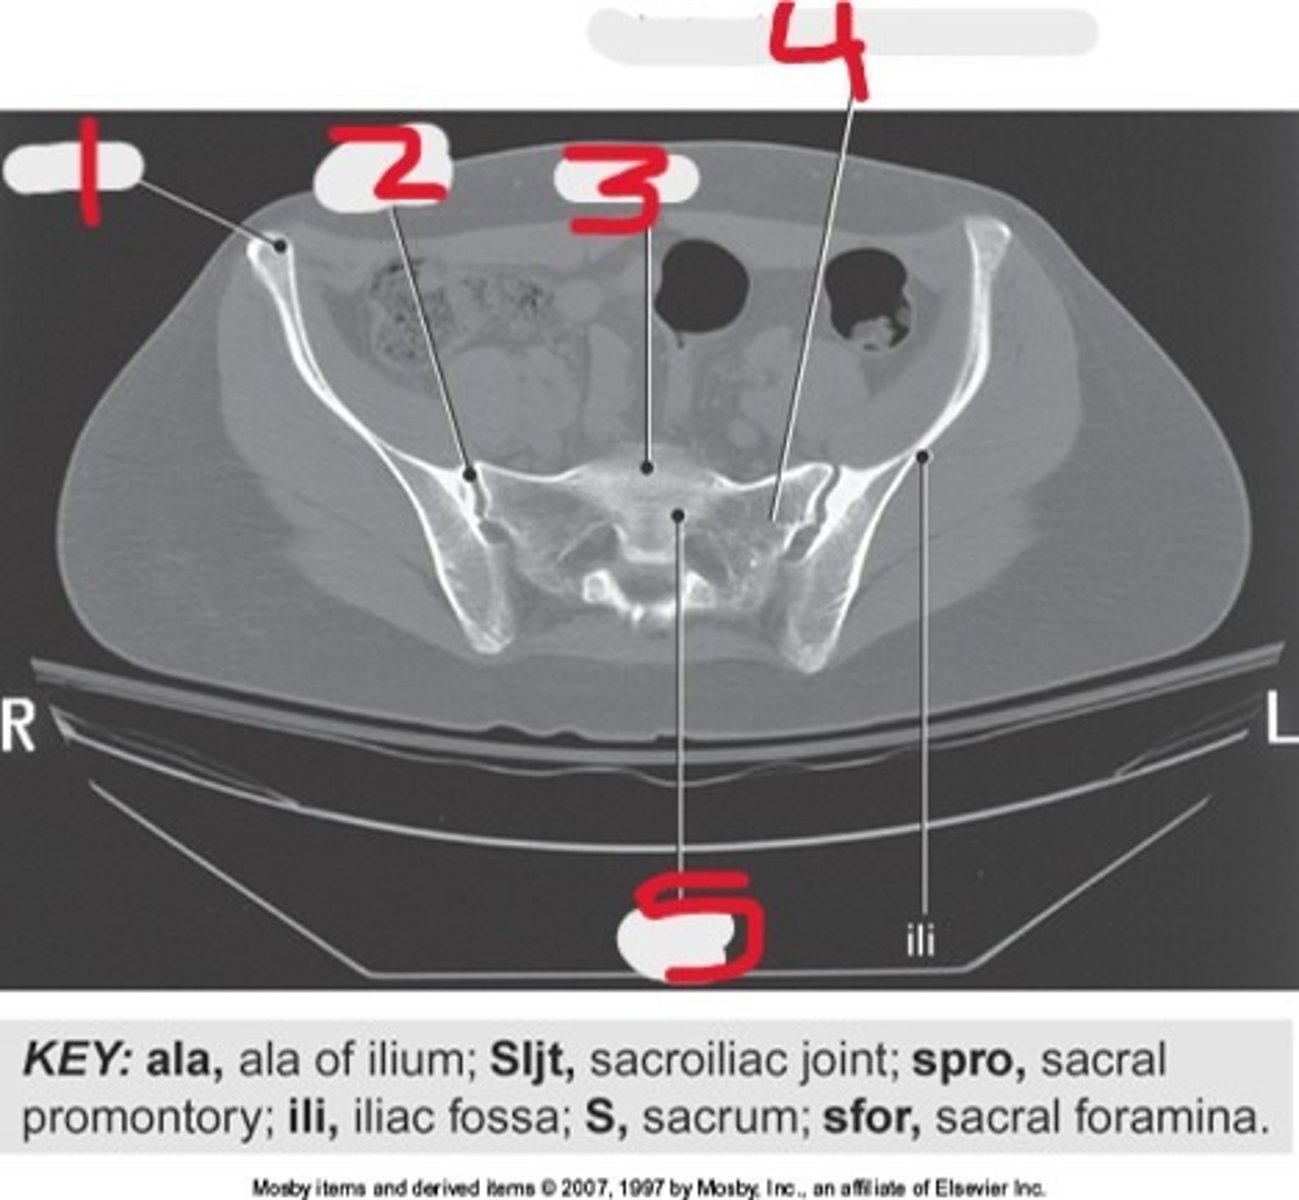

1) Ala of ilium

2) SI joint

3) Sacral promontory

4) Lateral mass of Sacrum

5) Sacrum

Name all numbered structures